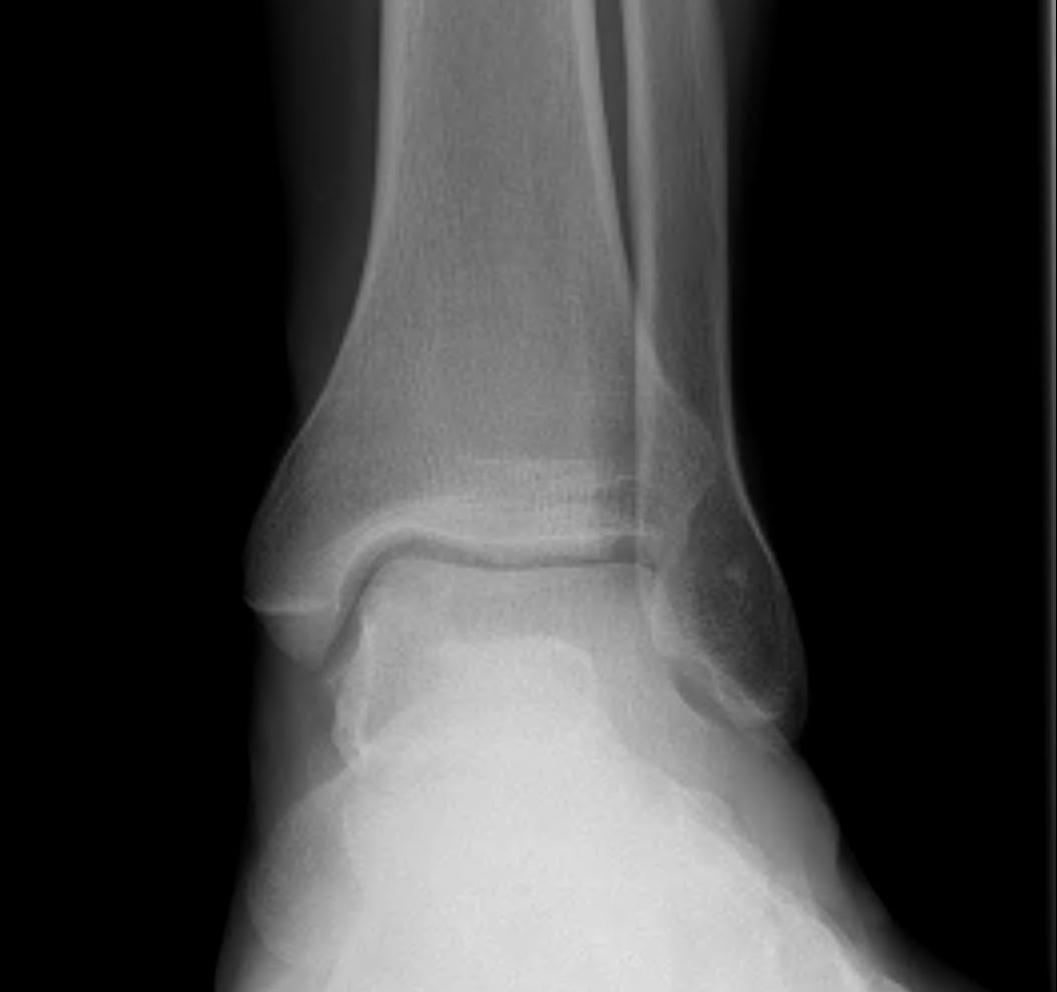

Fracture patterns

| Lateral malleolar fractures | Medial malleolar fractures | Bimalleolar fractures | Trimalleolar fractures |

Weber A - below syndesmosis Weber B - at syndesmosis Weber C - above syndesmosis |

Uncommon |

Fibular + medial malleolus Bimalleolar equivalent - fibular + deltoid ligament Fibular + posterior malleolus |

Fibular fracture + Medial malleolus fracture + Posterior malleolus fracture |